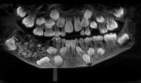

Después de la cirugía, las radiografías y las tomografías computarizadas revelaron que la masa tisular, que pesaba 200 gramos, contenía "múltiples estructuras radiopacas diminutas".

"Los tamaños de los dientes variaban de 1,0 mm a 15 mm y cada uno se asemejaba a un diente con una corona cubierta de esmalte y una estructura similar a una raíz", indicó el Colegio.